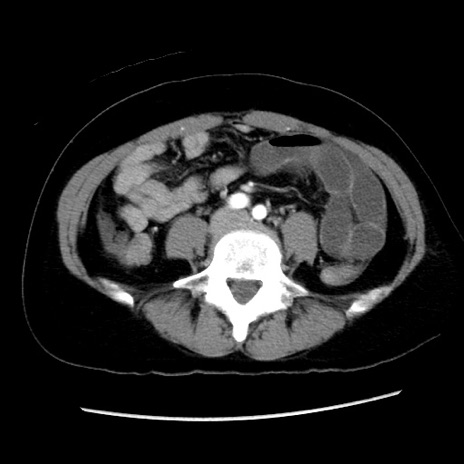

症例10(横断像)

【症例】 50歳代女性

【主訴】 腹痛

【現病歴】前日生レバーを食べた。今朝に排便あり。 昼前に突然発症の腹痛を生じ、当院救急外来を受診した。

【既往歴】 子宮筋腫にてで子宮全摘後

【身体所見】 意識清明、腹部:平坦、軟、下腹部やや左を中心に圧痛・反跳痛あり、筋性防御あり

【データ】WBC 7800、CRP 0.07